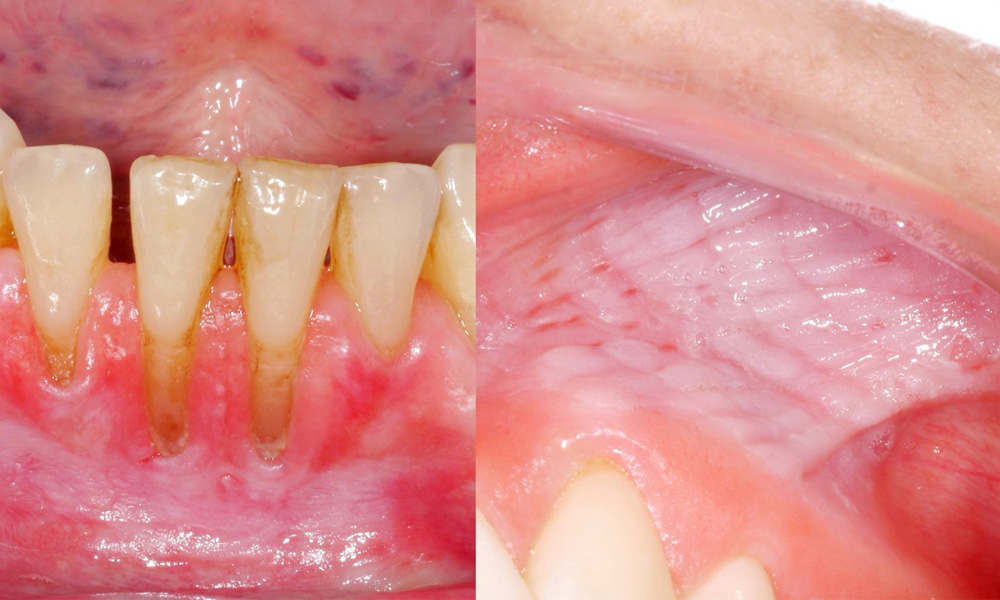

- Approximately 80% of those examined who consumed snus daily had snus-induced mucosal lesions.

- Approximately 20% of those examined who consumed snus daily had snus-induced gingival recession.